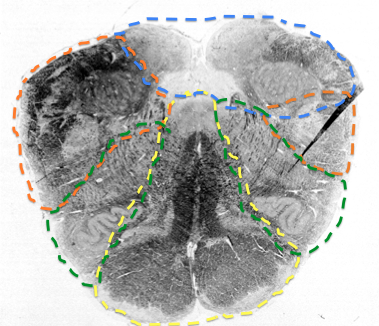

when does AICA first appear?

in rostral medulla when CN 8 comes in

in the medulla it just supples dorsal cochlear nucleus and the CN 8

What does AICA supply? until when?

AICA

lateral part of middle pons until the rostral pons section

purple

superior cerebellar artery

supplies the superior cerebellar peduncle area throughout the pons